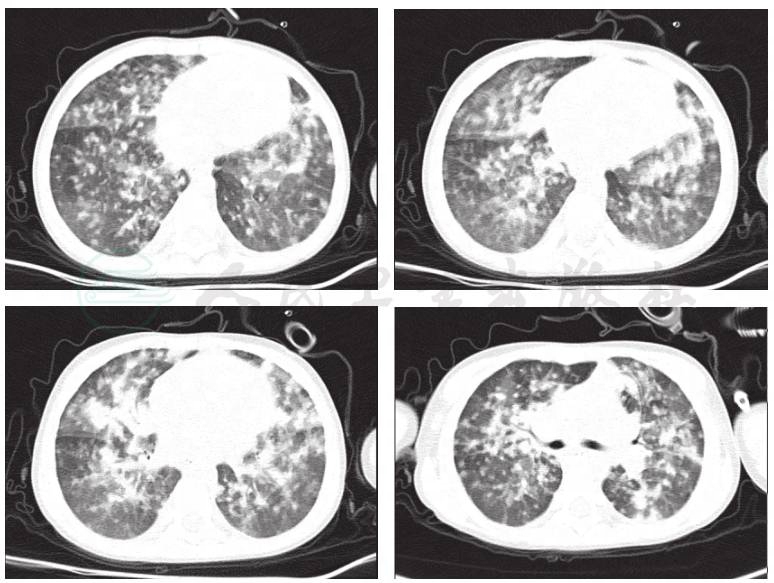

入院第5天,化验回报:患儿HIV-1型抗体阳性,结合患儿CD4+T淋巴细胞计数<32个/μl,此时考虑患儿存在艾滋病病毒感染;且患儿伴随咳嗽、发热及呼吸困难等表现,结合典型的影像学特点,即可诊断患儿系卡氏肺囊虫肺炎可能性大;立即予患儿加用复方磺胺甲 𫫇 𫫇唑治疗。同时,升级抗生素为亚胺培南西司他丁钠及万古霉素抗感染,并继续呼吸机辅助通气治疗,可维持患儿生命体征平稳。更改治疗方案后,患儿病情迅速好转。入院第11天,予患儿将呼吸机通气模式调整为CPAP。入院第12天,患儿面罩带囊吸氧下,生命体征平稳。入院第14天,复查胸部CT明显好转(图2)。予患儿拔除气管插管,鼻导管吸氧耐受,并逐渐下调氧流量至1L/min。复查血常规、肝功能、心肌酶等指标未见明显异常。CRP略高。入院第15天,予患儿停用亚胺培南。入院第17天,患儿体温平稳,予患儿停用万古霉素。入院第19天,患儿无发热,生命体征平稳,米卡芬净钠、复方磺胺甲 𫫇 𫫇唑及头孢哌酮舒巴坦治疗中,病情缓解,但肺部仍有炎症,转至当地医院继续巩固治疗。

图2 治疗14天后复查肺CT结果